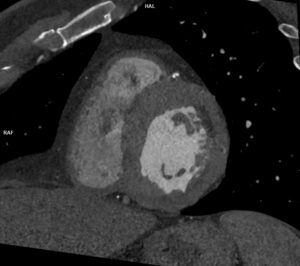

Video 3: achiziție axială T2 abdomen superior

Video 4: achiziție axială T1 abdomen superior

Video 5: achiziție axială T1 postcontrast

Video 6: achiziție coronală T1 postcontrast

Discuţie caz nr 60: Pacientul a efectuat examinare CT de urgență pentru sindrom icteric; la examinarea CT s-a pus în evidența creștere de calibru a căilor biliare bilateral cu aspect simetric cu decalibrare în hilul hepatic unde se pune în evidență o leziune densă, slab iodofilă; s-a recomandat completare cu examinare IRM. Examinarea IRM a evidențiat un colangiocarcinom periductal infiltrativ – tumoră Klatskin ce evoluează și la nivelul ductului cistic și la nivelul coledocului în jumătatea proximală (săgeți). Deasemenea, atât la examinarea CT cât și la examinarea IRM se pune în evidență creștere difuză a grosimii peretelui gastric ce este hipokinetic cu adenopatii perigastrice – endoscopia digestivă efectuată cu prelevare de biopsii a pus diagnosticul de limfom gastric infiltrativ sincron.

DE LUAT ACASĂ!!! Creșterea difuză sau localizată de calibru a cailor biliare la eco sau CT sugerează indicația de examinare IRM pentru caracterizare tisulară suplimentară a obstacolului: litiază sau leziune expansivă. Examinarea ultrasonografică este 100% fiabilă în diagnosticul litiazei biliare veziculare sau de căi biliare în cazul unui utilizator experimentat. Leziunile expansive de căi biliare sunt în general caracterizate prin IRM cu ajutorul achizițiilor T1 pre și postcontrast și de difuzie, iar achizițiile T2 ajută la localizare prin evidențierea locului de decalibrare a cailor biliare.